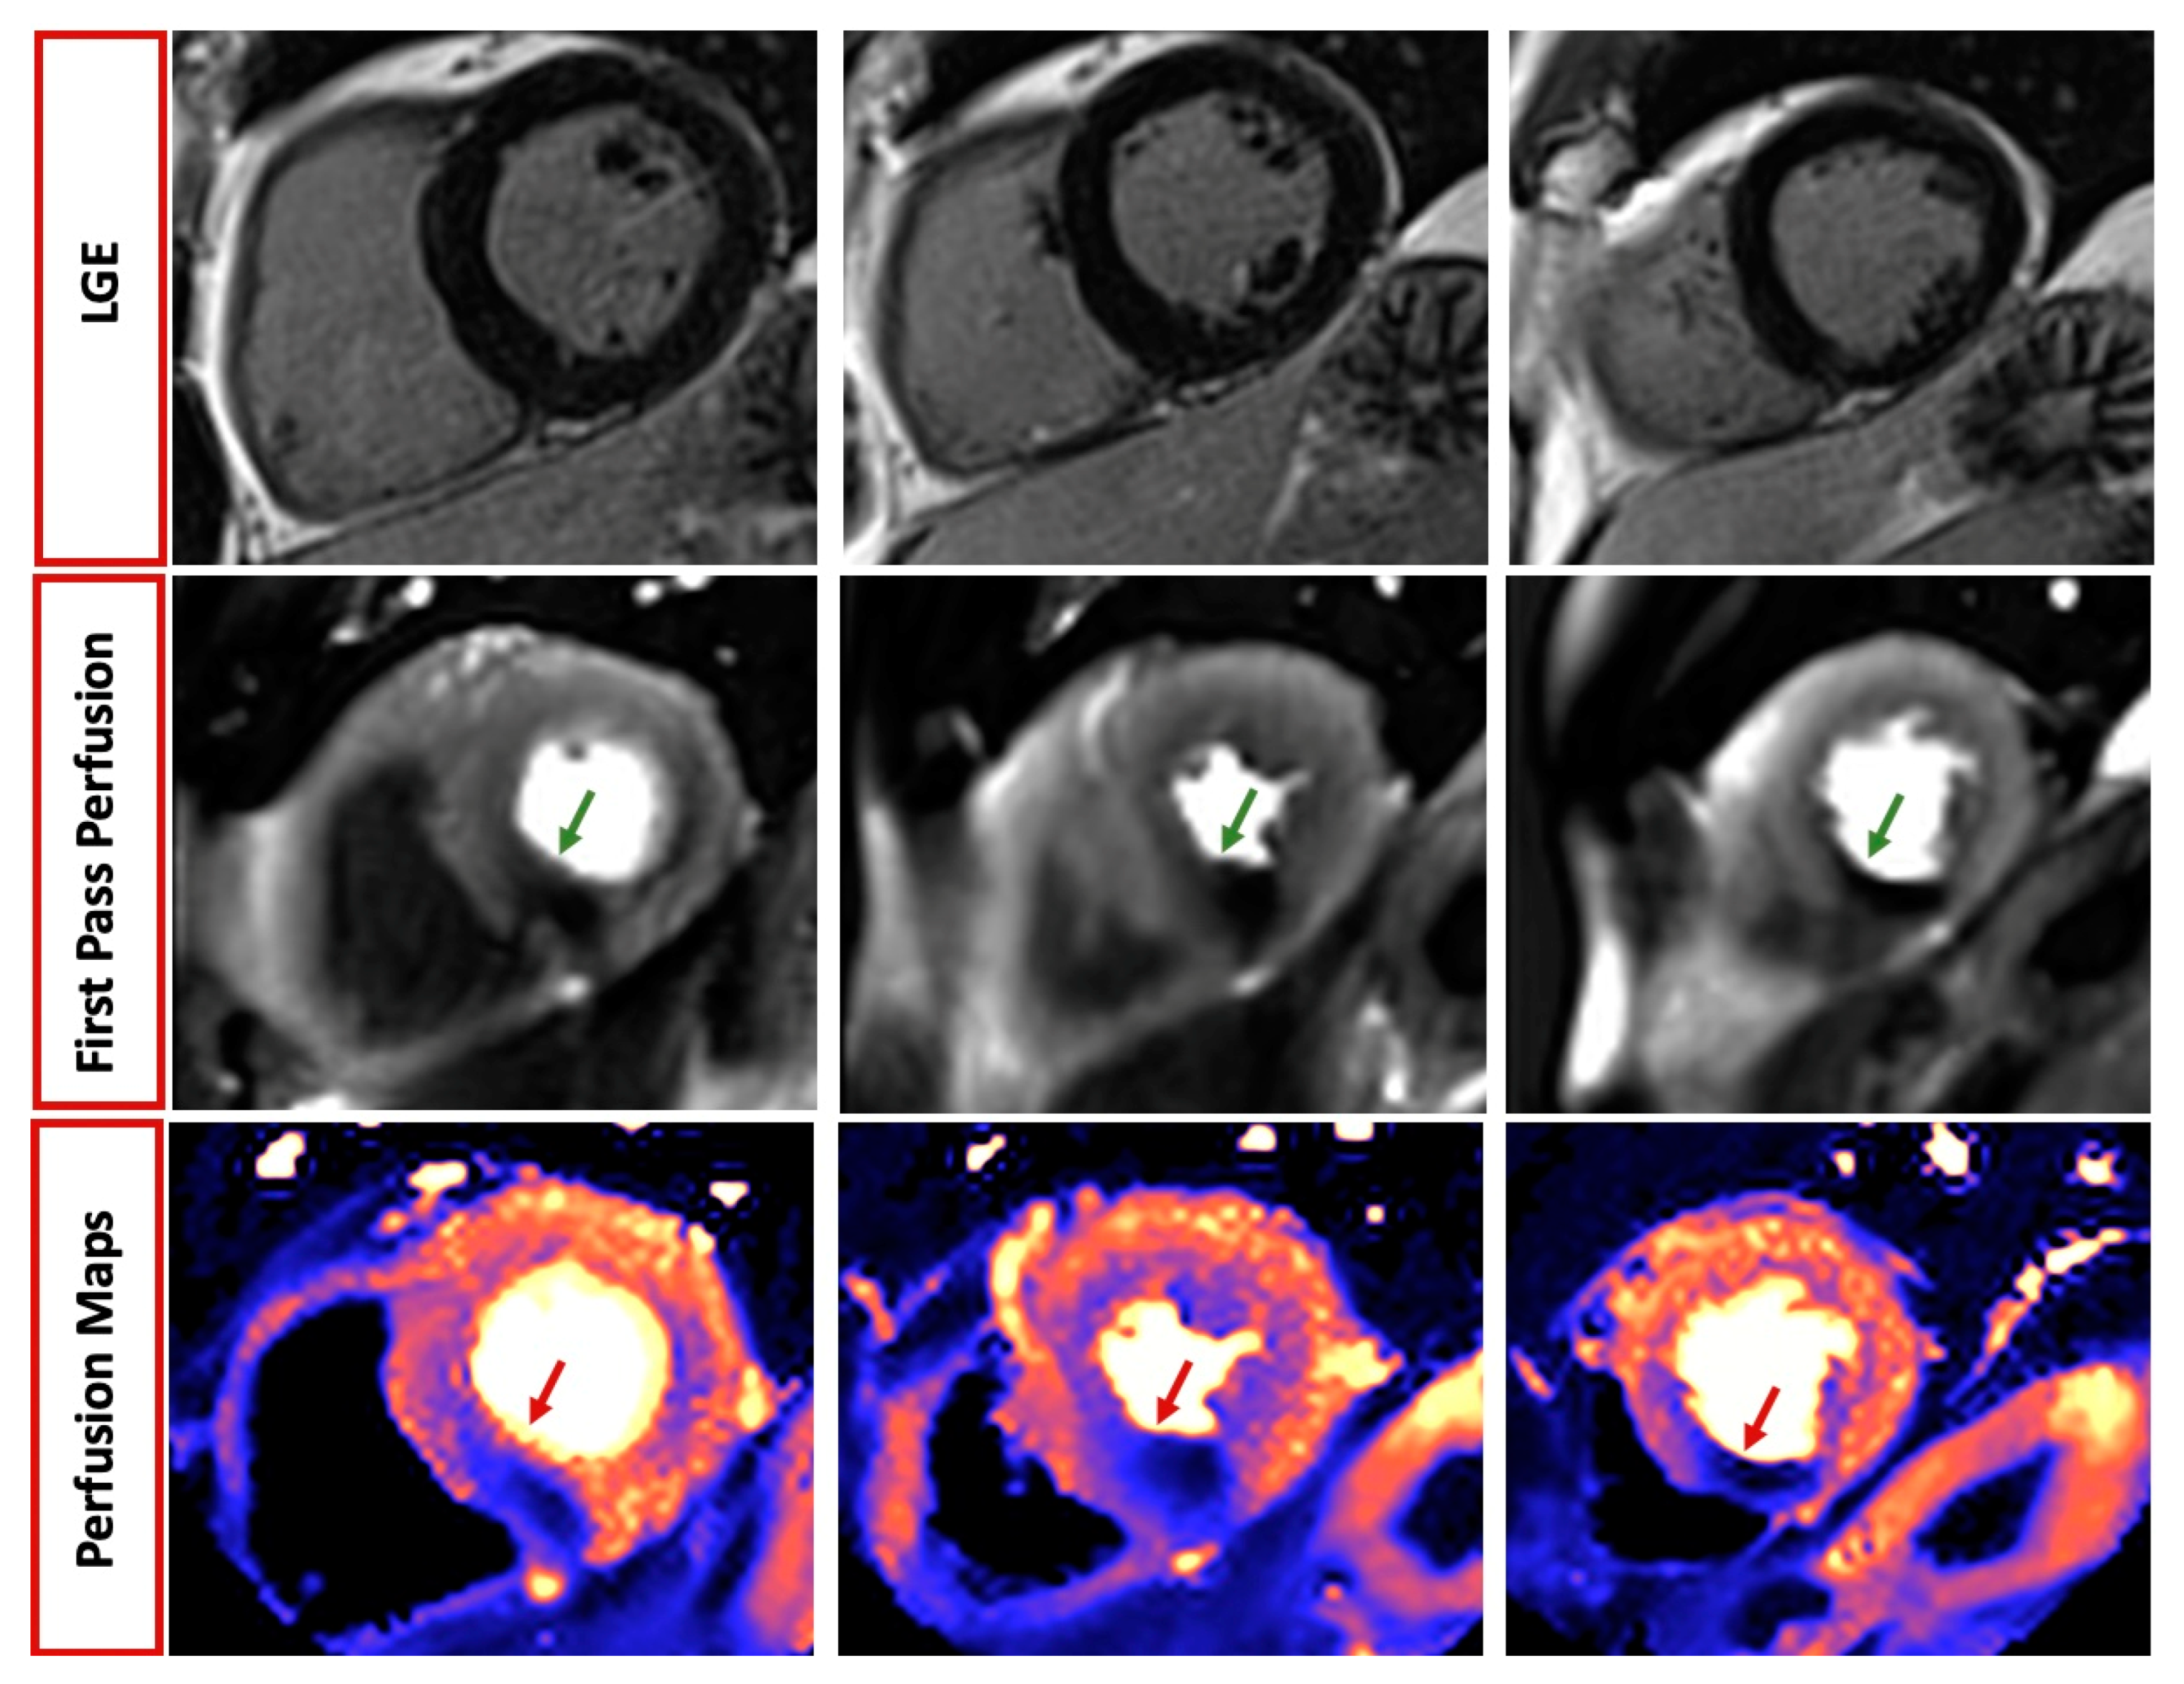

4.2. Coronary Artery Disease (CAD)